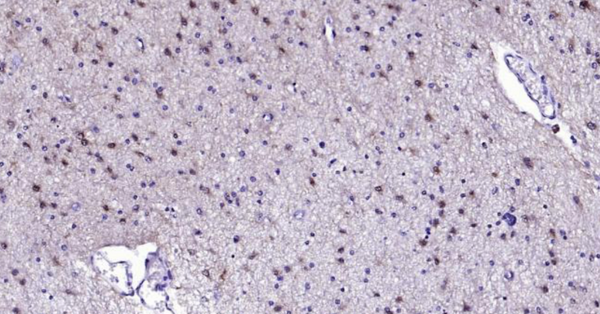

Immunohistochemical analysis of paraffin embedded human brain tissue slide using IHC0110H (Human S100B IHC Kit).